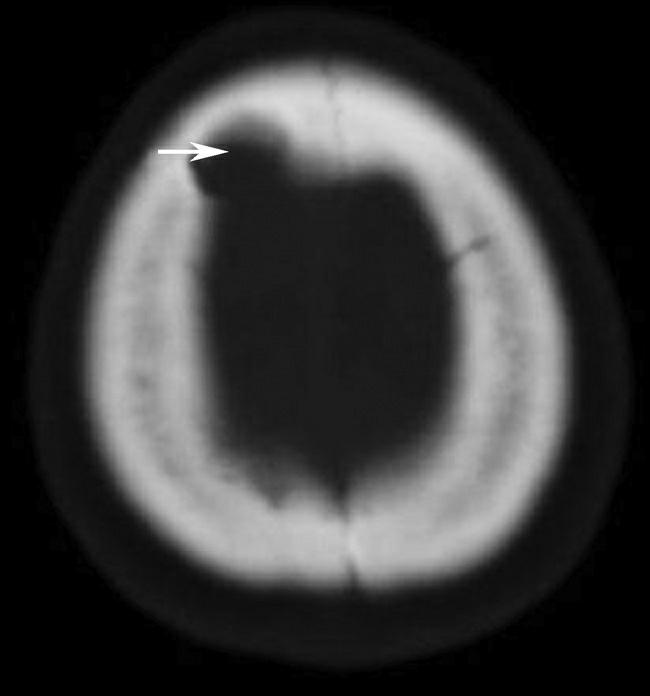

Alberta卒中项目早期CT评分(Alberta stroke program early CT score,ASPECTS)是一种评价急性缺血性卒中患者大脑中动脉供血区早期缺血性改变的简单、可靠、系统化的方法,是常用的脑卒中评定量表之一,可对缺血性病变快速进行半定量评价,有助于判定溶栓效果和远期预后。该评分主要基于CT平扫,具体分区如下(图1-2-76)所示,即选取大脑中动脉供血区2个层面。分区后共10个区域,每个区域记1分。评分时任何区域只要有低密度灶,则扣除该区域得分。正常脑ASPECTS评分为满分(10分),若MCA供血区广泛梗死累及全部区域时,则ASPECTS评分为0分。

图1-2-76 ASPECTS评分脑组织分区

A.在基底节层面(即丘脑和纹状体平面),分为各级分支M 1 、M 2 、M 3 、岛叶(缩写I)、豆状核(缩写L)、尾状核(缩写C)和内囊(缩写IC)后肢等7个区域;B.在基底节以上层面(基底节层面上2cm),包括M 4 、M 5 和M 6 。